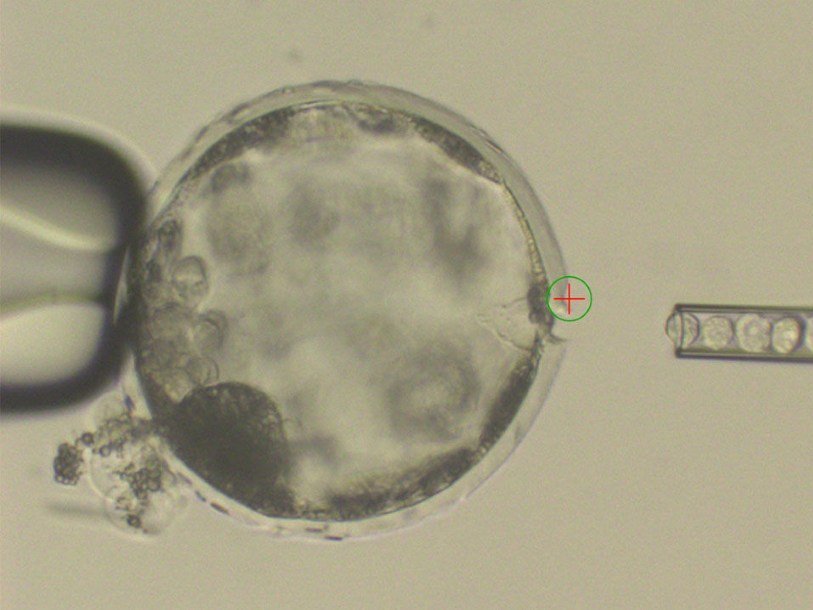

Ученые из Института биологических исследований Солка в Сан-Диего провели эксперимент по выращиванию человеческих клеток в эмбрионах свиньи.

Для этого они ввели эмбрионам индуцированные плюрипотентные стволовые клетки (iPS-клетки), а затем имплантировали эмбрионы самкам свиней и следили за их развитием в течение месяца. Хотя ученые пересадили около двух тысяч эмбрионов, выжили в месячный срок всего 186 из них, да и то некоторые развивались медленнее нормы. Однако выжившие человеческие клетки внутри них обнаружились. Ведущие авторы работы Хуан Карлос Исписуа-Бельмонте (Juan Carlos Izpisúa Belmonte) и Цзюнь У (Jun Wu) считают полученный результат обнадеживающим.